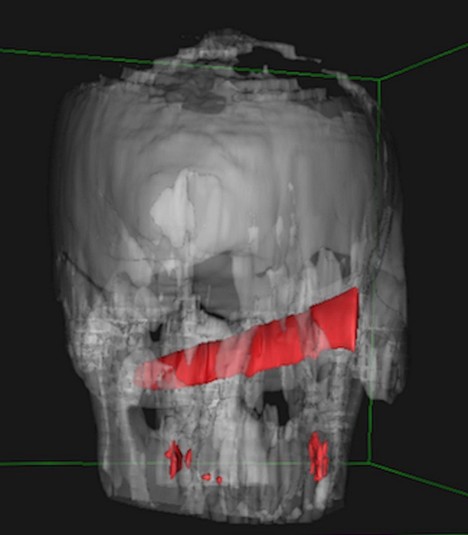

Рентген показав, що ніж зайшов на 10 см в голову, але не зачепив жодної артерії

Удар ножем в око він отримав під час п'яної бійки в барі. Після цього потерпілий як ні в чому не бувало відправився додому спати. Наступного дня чоловікові все ж довелося відвідати медичний заклад. Леза він не помітив, однак голова і очі дуже боліли. Рентген показав, що ніж зайшов на 10 см в голову, але не зачепив жодної артерії. Лікарі навіть вирішили перенести операцію на чотири дні, поки оформлялися необхідні документи.